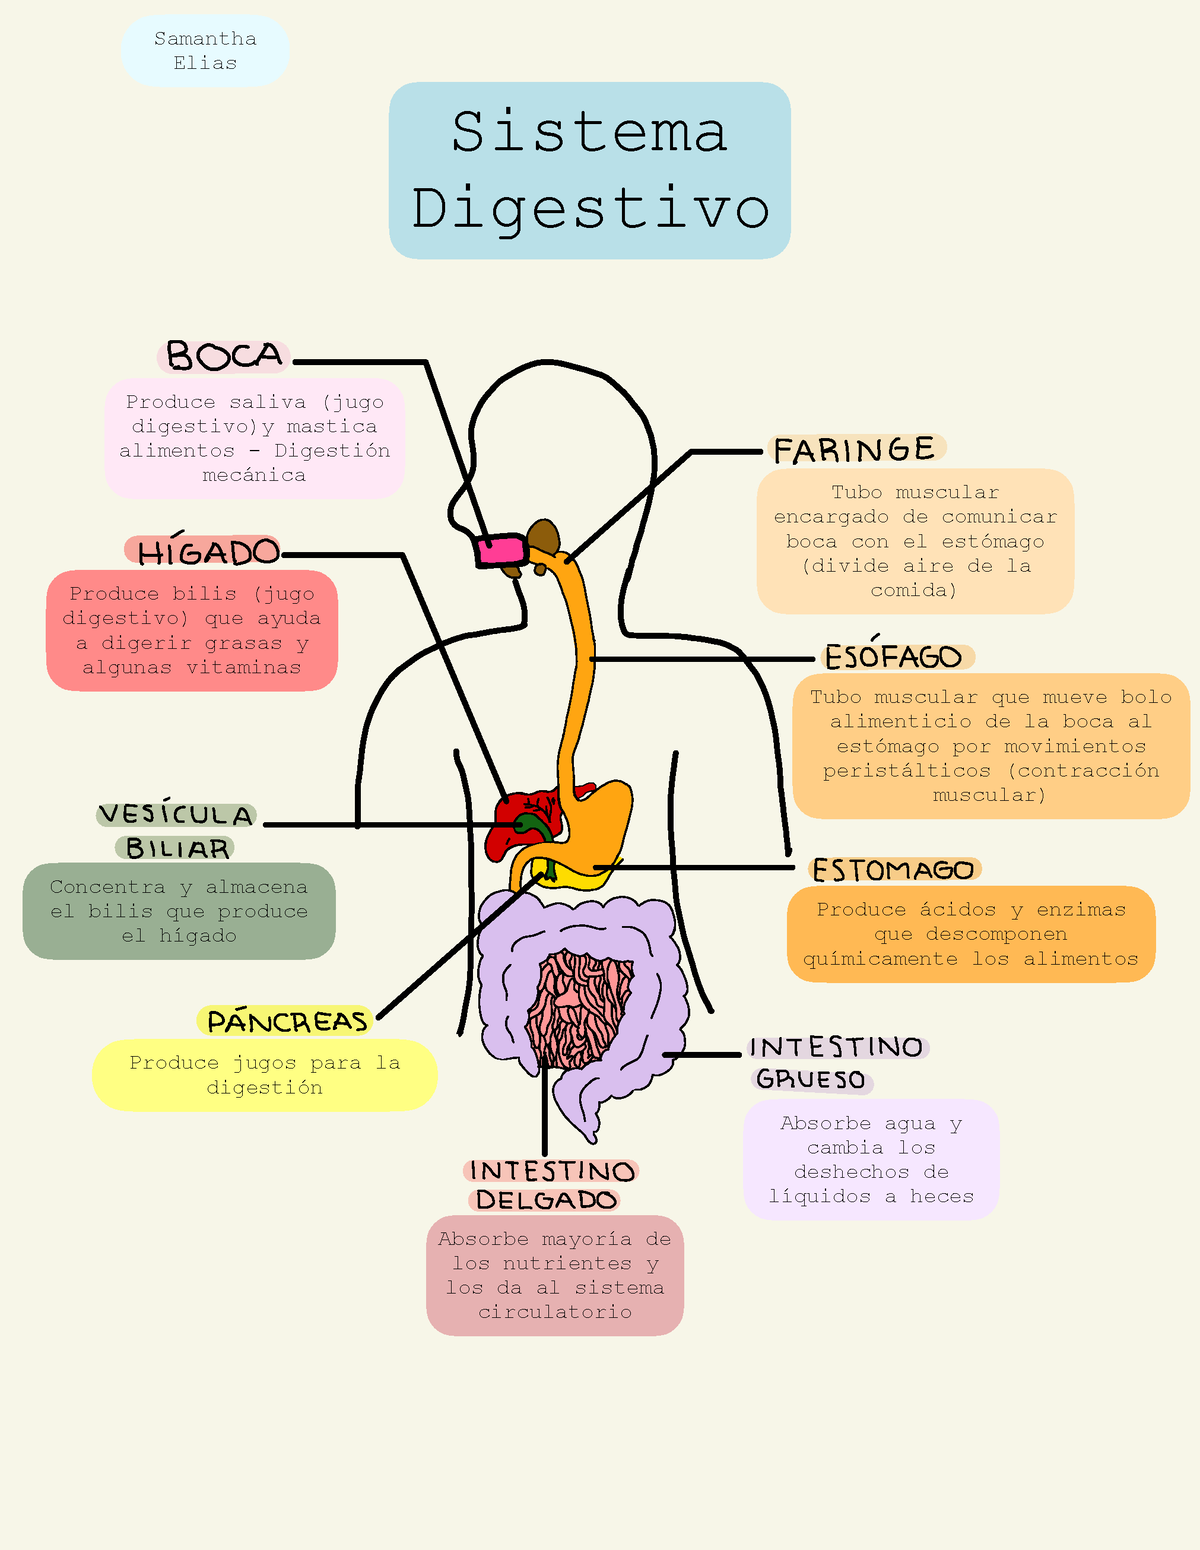

Diagrama Del Sistema Digestivo - Absorbe Mayoría De Los Nutrientes Y

www.studocu.com

www.studocu.com